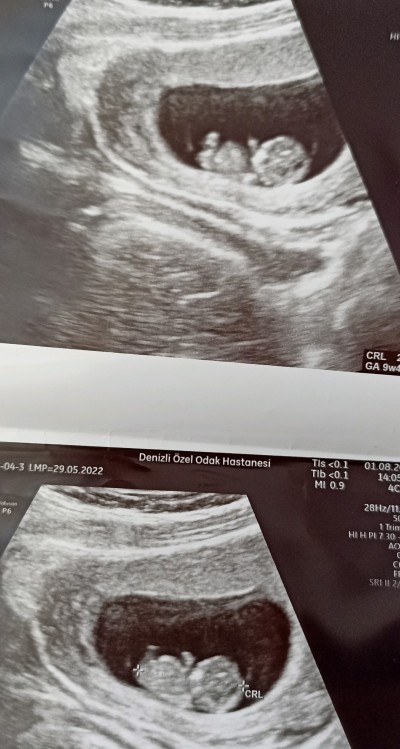

Arkadaşlar Cinsiyet tahmini yapabilir misiniz ?

Çok küçük canım bence daha belli değil fotoda

Kafa şekli yuvarlak olunca kız derler benim de bebeğim seninkine benziyor ve kız ☺️ sağlıkla gelsin

Bemce erkek sagliqli olsun